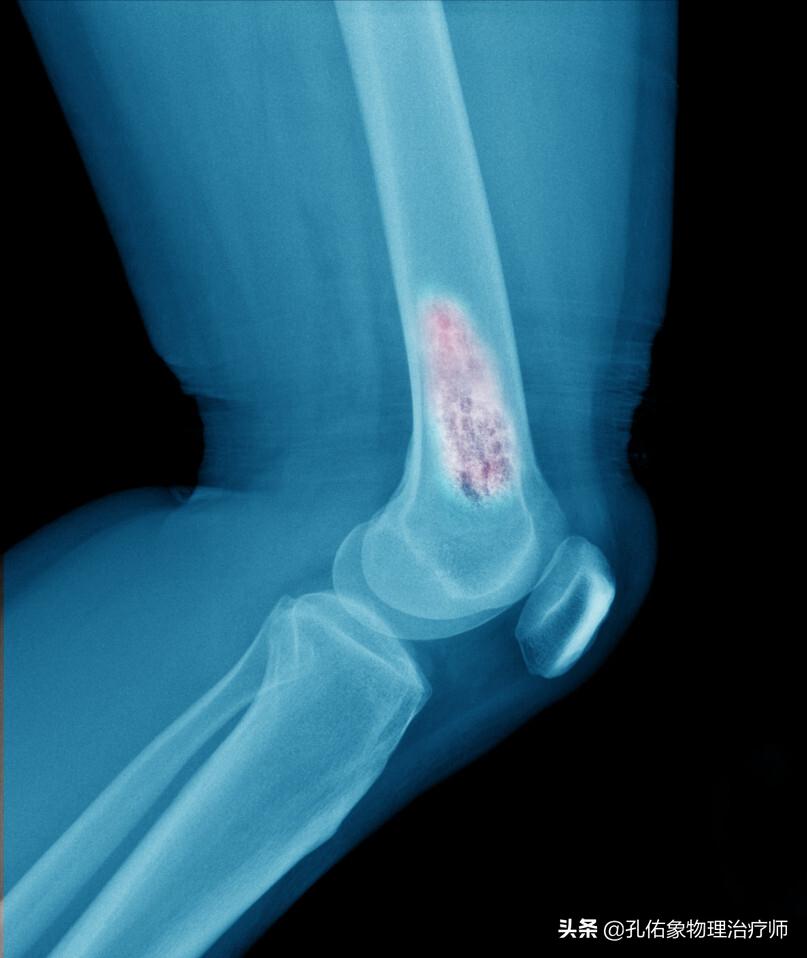

2.案例二:中年女性,常年在家务农,从事重体力活动,出现膝关节疼痛几年,一直想着是风湿病,忍忍算了,结果逐渐加重,才到当地县医院住院治疗,被认为是膝关节骨性关节炎。

经过几番折腾,治疗也未见起色,才来到省级医院看,一查竟然是大腿骨上长有一个良性肿瘤。